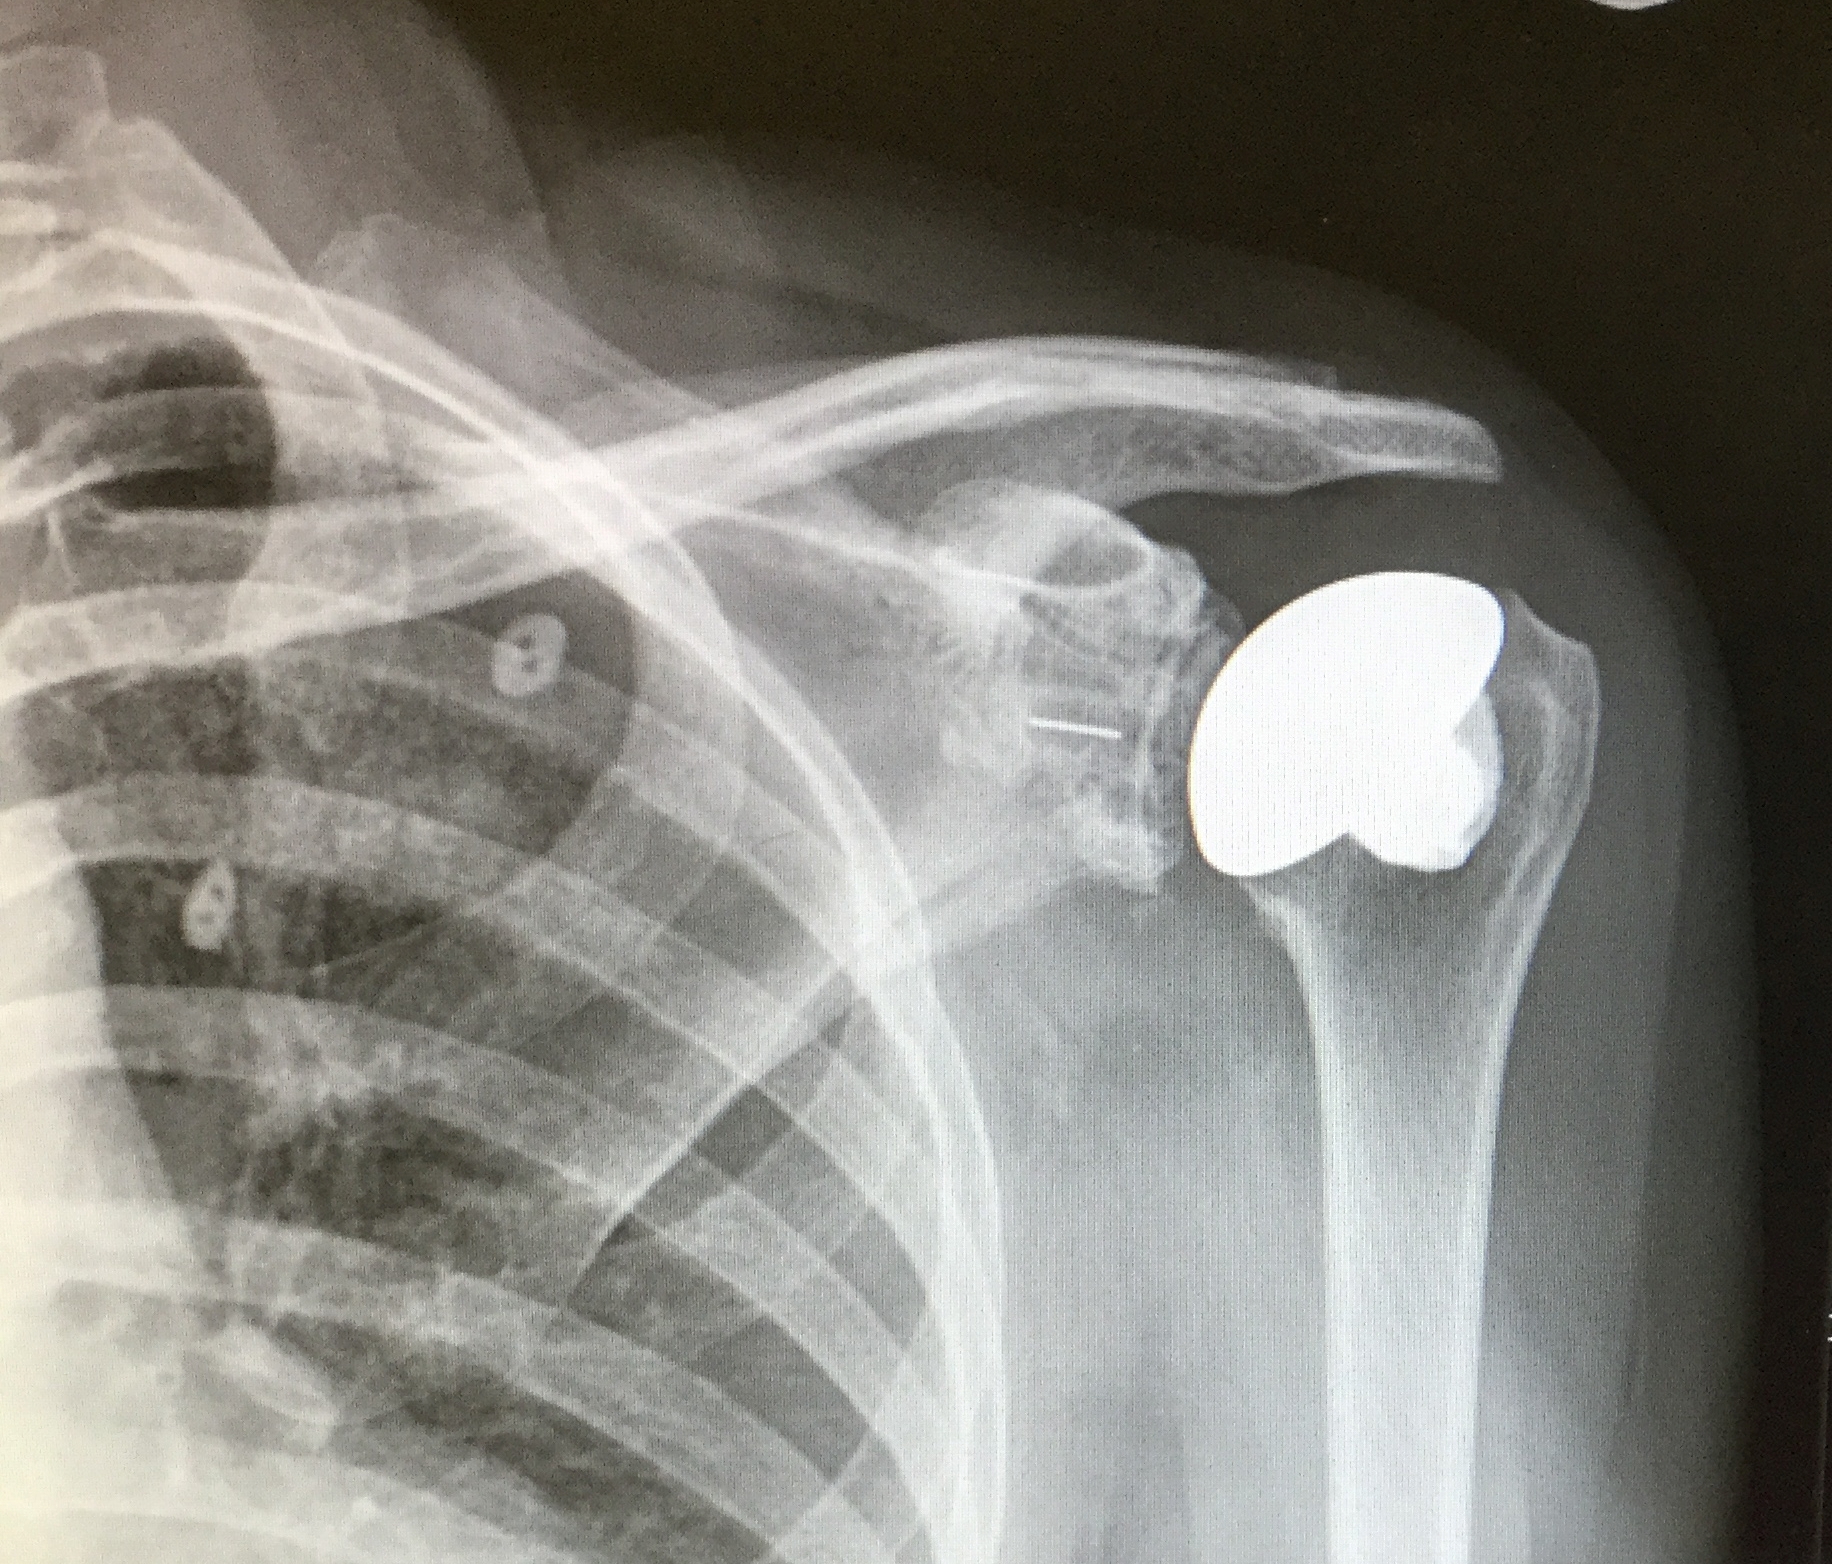

Gallery 27 Wednesday Jan 2016 Original size at 1832 × 1564 ≈ Leave a comment My X-Ray after Replacement Please share this: Email a link to a friend (Opens in new window) Email Tweet Share on WhatsApp (Opens in new window) WhatsApp Like Loading...